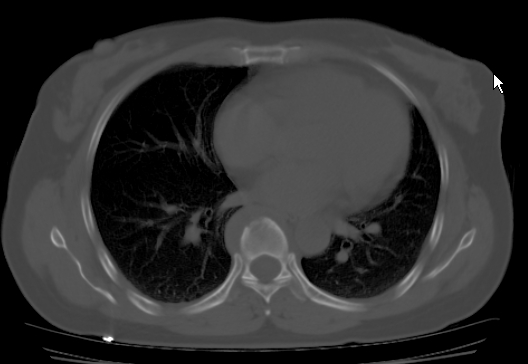

标题: CT25227:背部疼痛伴双侧胸壁痛2月,食欲差。 [打印本页]

标题: CT25227:背部疼痛伴双侧胸壁痛2月,食欲差。

肺结核并胸椎结核?请各位高手指教。

用椎体的条件来扫胸椎呀!考虑1左侧胸膜小结节形成2椎体结核并冷脓肿形成

考虑胸椎结核并椎旁软组织肿胀。

椎旁软组织肿胀。

考虑胸椎结核并椎旁软组织肿胀。 支持